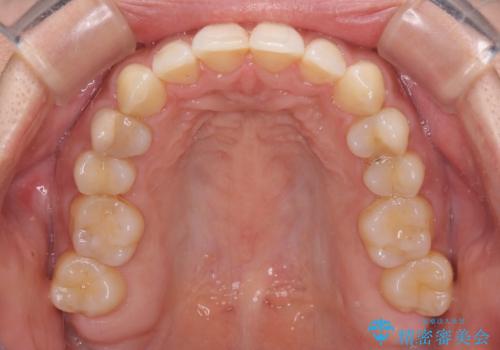

沖縄から飛行機で通院 インビザラインによる矯正治療

- 定期的に東京に来るので、沖縄から矯正治療で通院したいとのことで来院された患者様です。

歯列不正は軽度であったので、応急処置の少ないインビザラインにて矯正治療を行うこととしました。